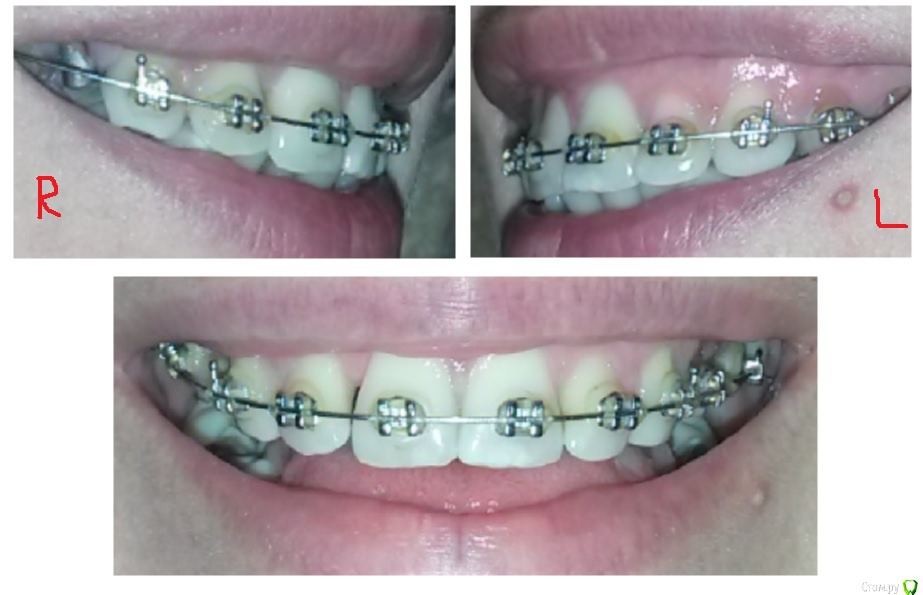

Здравствуйте! Мне 34 года, ношу брекеты 10 мес. на ВЧ (месяц как перешли на дугу 17/22), ориентировочный срок выравнивания (заявленный ортодонтом) – 1-1,5 года. Лечение без удаления, но на 2 корнях установлены штифты под коронки (на «4» справа и «5» слева).

1)     Изначально думала, что моя проблема – неправильный угол/наклон двоек. Но на сегодня справа имею внушительный черный треугольник (см.фото) между "1" и "2": размер 2*4*4 мм. Врач сказал, что это форма зубов и скрыть дефект можно только фотополимерами. Где-то понимаю, что десна вряд ли отрастет (если её там отродясь не было), но и зубы пломбами портить не хочется. Даже расстроилась – выбрала брекеты, чтобы, выравнивая, сберечь зубы, а с таким «эффектом»  можно было ставить виниры или ходить с кривыми (слева, получается, тоже будет треугольник).

2)     Вторая проблема – зубы быстро/легко/постоянно перемещаются с правой стороны, но слева за последние 8  мес. (из 10 мес.), при наличии небольшого «зазора» между 3 и 4, практически не двигаются. На  срок лечения в 1-1,5 года уже смотрю скептически. Сделала новую ОПГ –  врач сказал, что всё отлично, просто нужно ждать.

3)     Через раз врач при установке дуги смещает примерно на 0,5 см её центр в правую сторону  -  т.е. 3-4 мес я хожу с центром дуги, совпадающим с центром зубов, потом 3-4 мес. со смещенным.